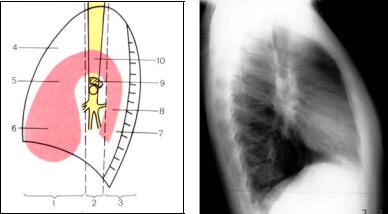

При рентгенологическом исследовании в средостении выделяют три вертикально расположенных отдела: передний, центральный и задний, а также три этажа: верхний, средний и нижний. Деление это условное и анатомические границы отсутствуют (рис. 31). Оно предназначено для систематизации и упрощения диагностики патологических образований.

а

б

Рис. 31. Схема (а) и рентгенограмма правая боковая (б) с обозначением органов средостения:

1– переднее средостение;

2– центральное средостение;

3– заднее средостение;

4– ретростернальное пространство и локализация вилочковой железы;

5– восходящая аорта;

6– сердце:

7– ретрокардиальное пространство;

8– грудная аорта;

9– левая ветвь легочной артерии;

10– дуга аорты